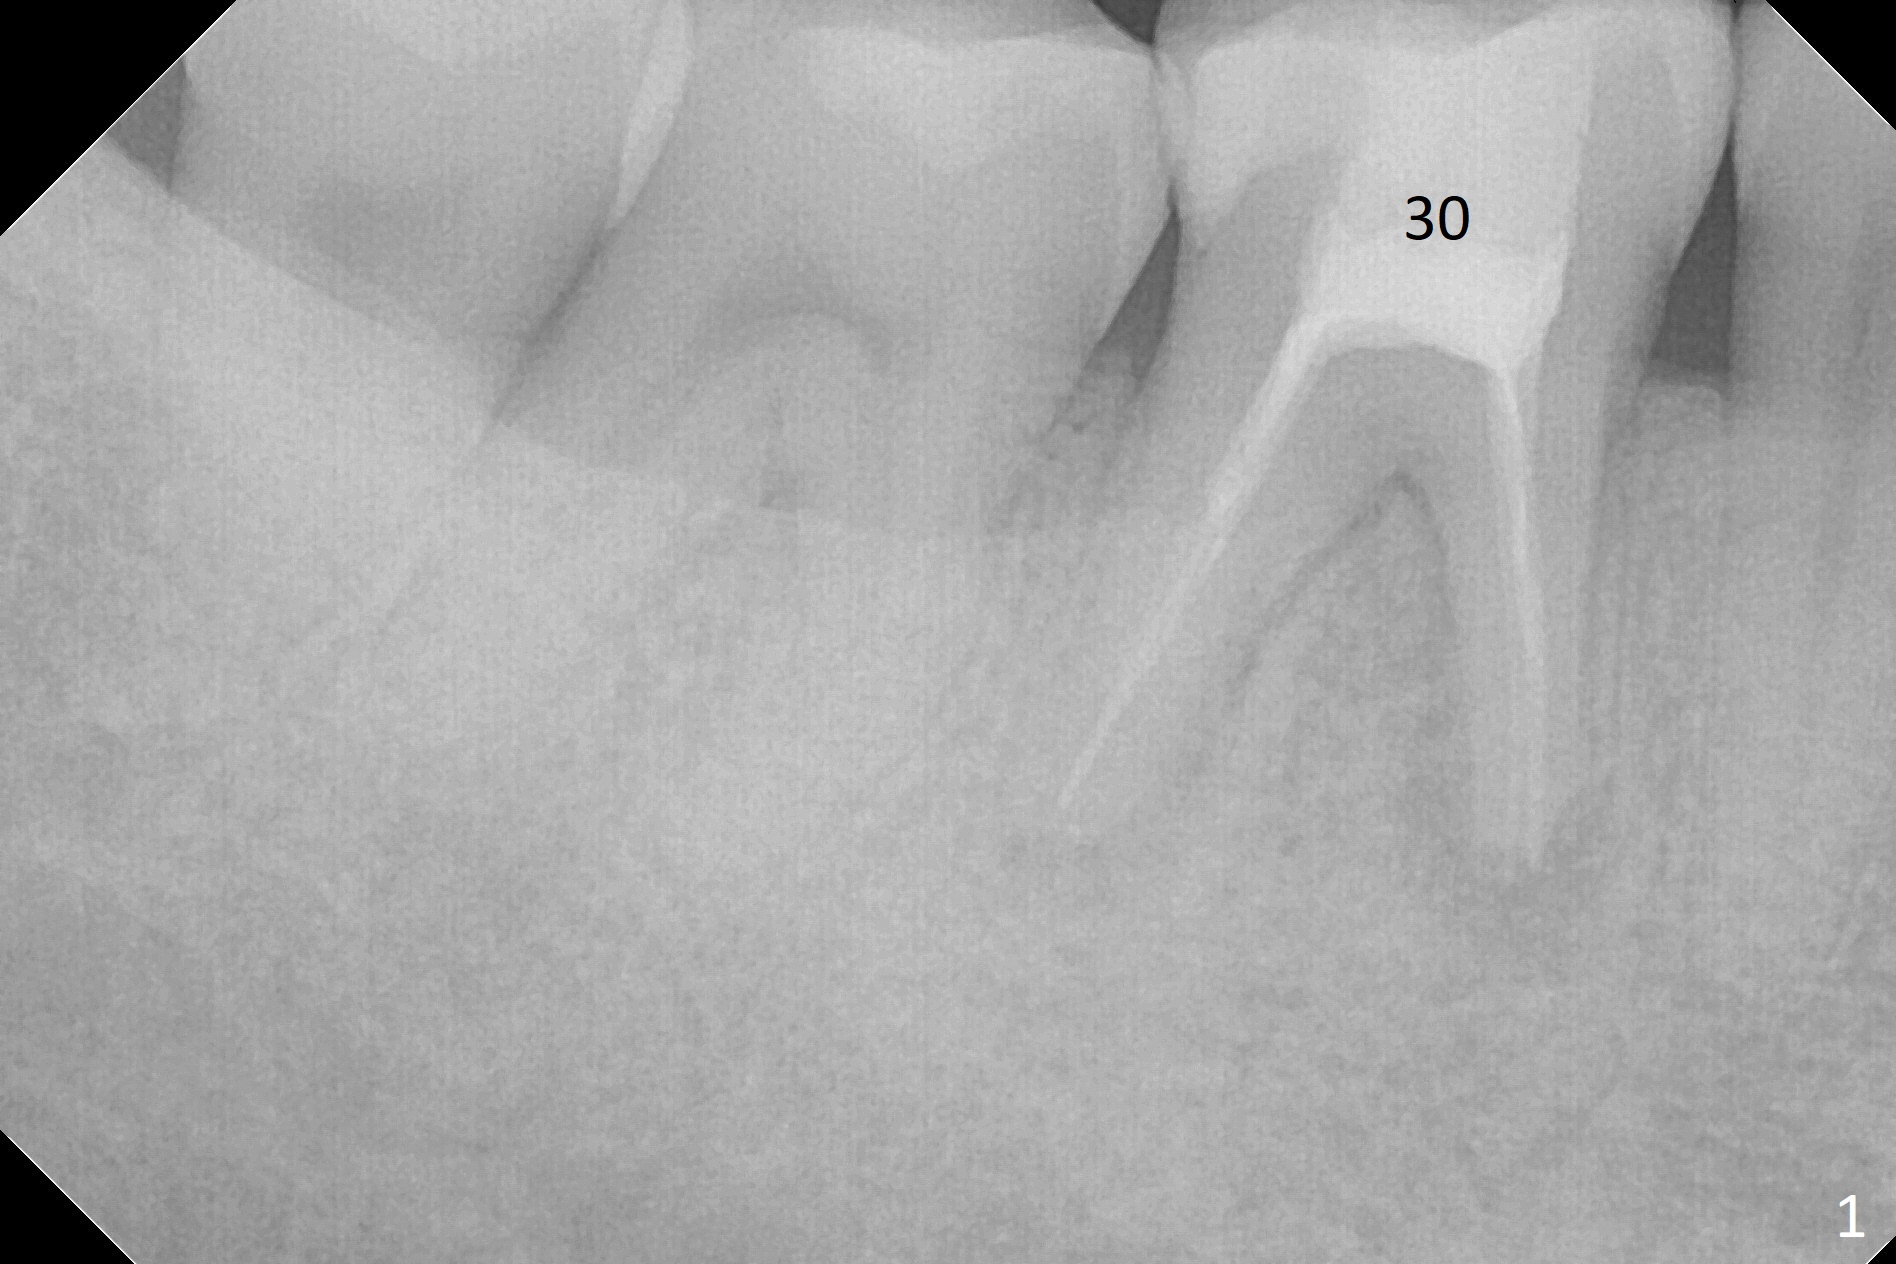

A 45-year-old man fractures the distolingual cusp of the tooth #30 subgingival (Fig.1). In fact RCT restores the septal bone, as compared to Fig.2. Initial depth at the septum is 13 mm (Fig.3).